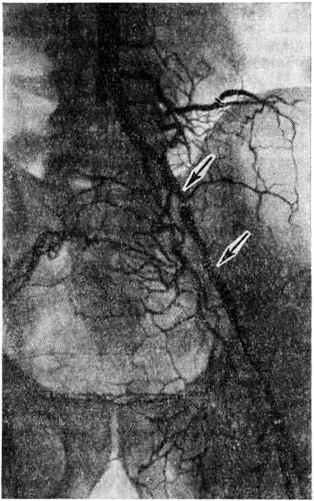

Топическую картину поражения можно установить пробой изотопной и рентгеноконтрастной ангиографии. Изотопная ангиография (смотри полный свод знаний) осуществляется пробой внутривенного введения технеция 99-м. Из методов рентгеноконтрастного исследования предпочтение следует отдать транслюмбальной пункционной аортографии (смотри полный свод знаний), при которой возможно получить изображение не только аорты, но и дистального сосудистого русла конечностей. Именно аортография выявляет локализацию и протяжённость поражения (рисунок 4—6), однако её следует проводить только при решении вопроса об оперативном лечении больного.

Рис. 4.

Аортограмма больного с синдромом Лериша при атеросклеротическом поражении бифуркации аорты и общих подвздошных артерий: окклюзия правой общей подвздошной артерии; стенозы левой подвздошной артерии указаны стрелками.